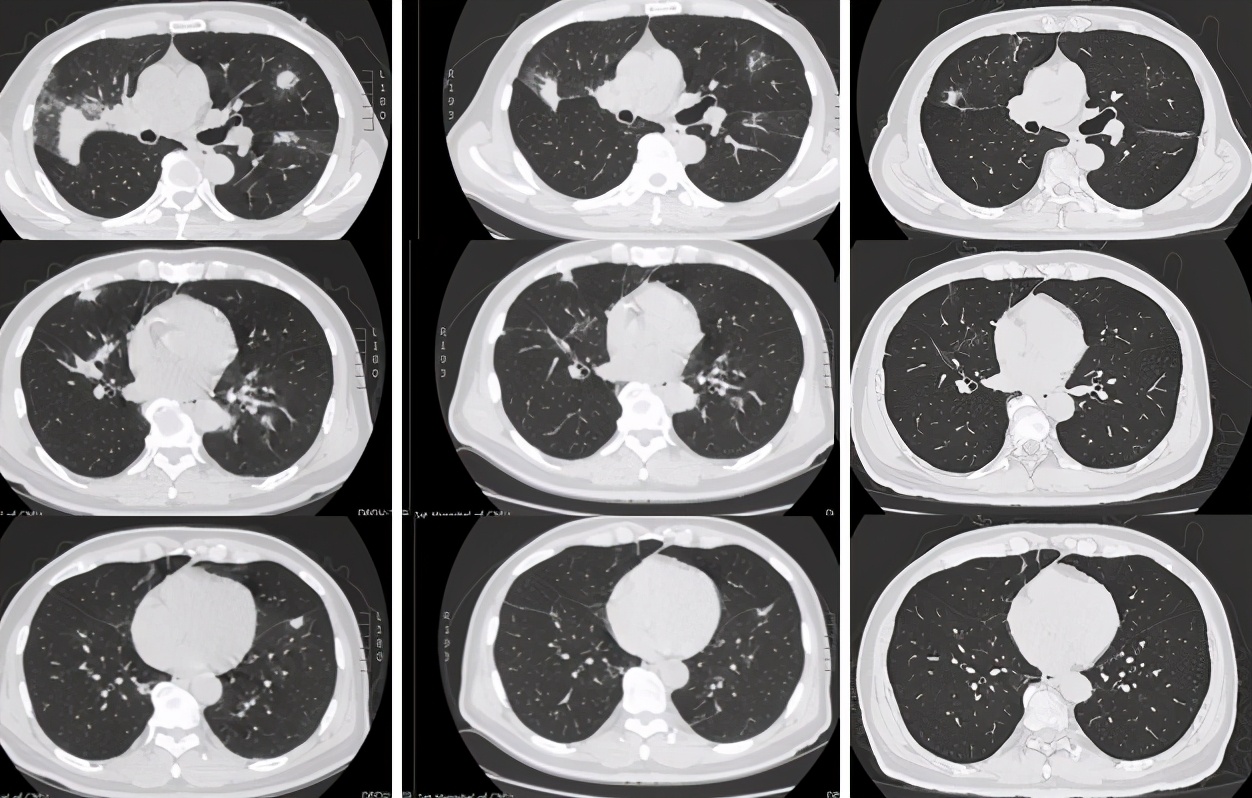

1年前肺CT(2020.3.12)

本次发病时肺CT(2021.2.18)

外院治疗后肺CT(2021.3.5)

黎庶教授(放射科)点评: 该患者的右肺门可见一团片影,其内可见正常走形的支气管,右肺上叶后段临近叶间胸膜处又可见一团片影,类圆形,边缘有毛刺,周围类似有晕征,除此之外肺内还可见多发散在的结节,边缘不规则。上述病灶经抗炎治疗没有改善,似乎有所加重。根据目前这些资料,无法确定感染还是非感染,一元论还是两元论,但肝癌肺转移肯定不是,因为肺内转移瘤不会形成大片状的改变,影像学不支持肝癌肺转移。肺CT改变更倾向于非感染,病灶沿支气管血管束旁和胸膜下分布,是多发的多种形态的,MALT淋巴瘤有这种特点,除此之外,炎性肌纤维母细胞瘤也有这种特点,血管炎、肉芽肿性病变也可出现。肺CT病变还有一个特点是既有实质改变又有间质改变,感染性疾病中TB、NTM和隐球菌都可以出现这种影像学改变。将肺脏和肝脏结合在一起分析,淋巴瘤可以同时多器官受累,风湿免疫系统疾病也可能。

激素治疗前后肺CT